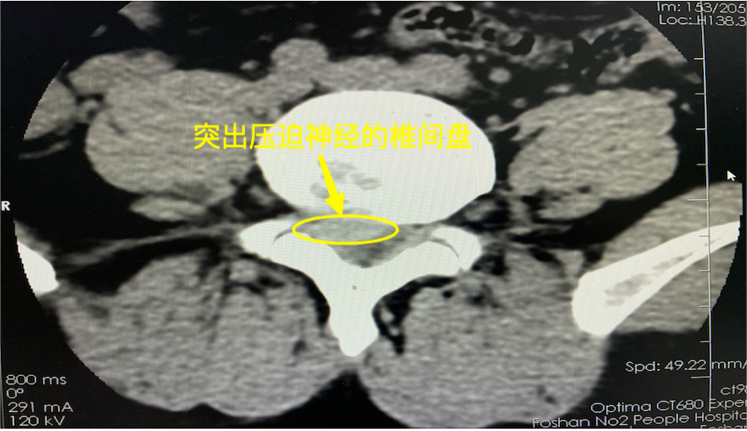

随后,他就来到了佛山市第二人民医院骨二科,完善了术前腰推CT显示:腰5/骶1 椎间盘向右后方脱出,合并椎管狭窄,呈轻度钙化。

术前术后CT对比可见突出椎间盘已被成功摘除